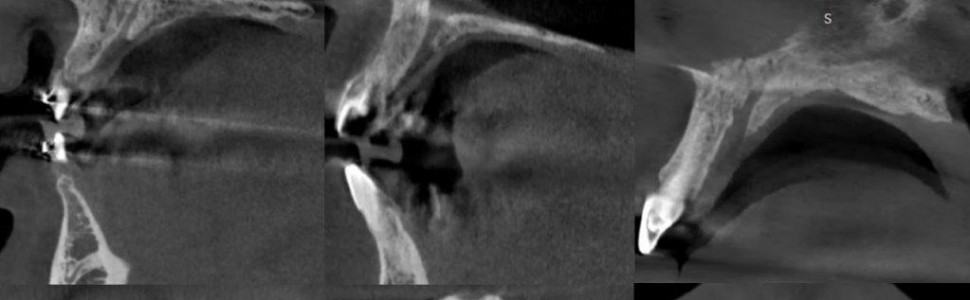

Torbiel kanału przysiecznego to jedna z najczęstszych torbieli w obrębie kości szczęk. Zmiana patologiczna jest wykrywana przypadkowo, podczas rutynowych badań radiologicznych lub w związku z objawami, takimi jak rozdęcie wyrostka czy dolegliwości bólowe, lub w przypadku zakażenia i zropienia. W niniejszej pracy przedstawiono metody diagnostyki i leczenia pacjentów z torbielą kanału przysiecznego.

The incisive canal cyst is one of the most common cysts in the jaw bones. The lesion is found incidentally during routine radiological examinations or in association with symptoms such as distension of the alveolar process, pain or in case of infection and purulence. This study presents methods of diagnosis and treatment of patients with incisive canal cysts.